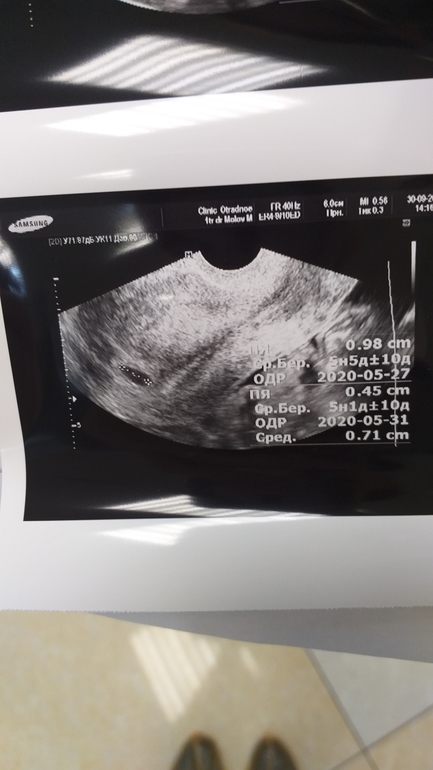

Девушки, гляньте узи. 2 графы - по одной срок 5+5 нед, по другой 5+1нед и ПЯ то 0,98см, то 0,45см - в итоге средний размер 0,71см и средний срок 5+3

Пошла потому что яичники болят - в ту среду ПЯ было 4мм и 70-75мл жидкости, огромные яичники. Сказали следить...

По месячным сейчас 4+6нед. Никого и ничего еще не нашли, пойду на следующей искать содержимое ПЯ. Становится страшно и волнительно. Вообще и узист дядька какой-то - датчик еле-еле вставил, смотрел в серую муть и что-то мне говорил... Как-будто от себя...  .